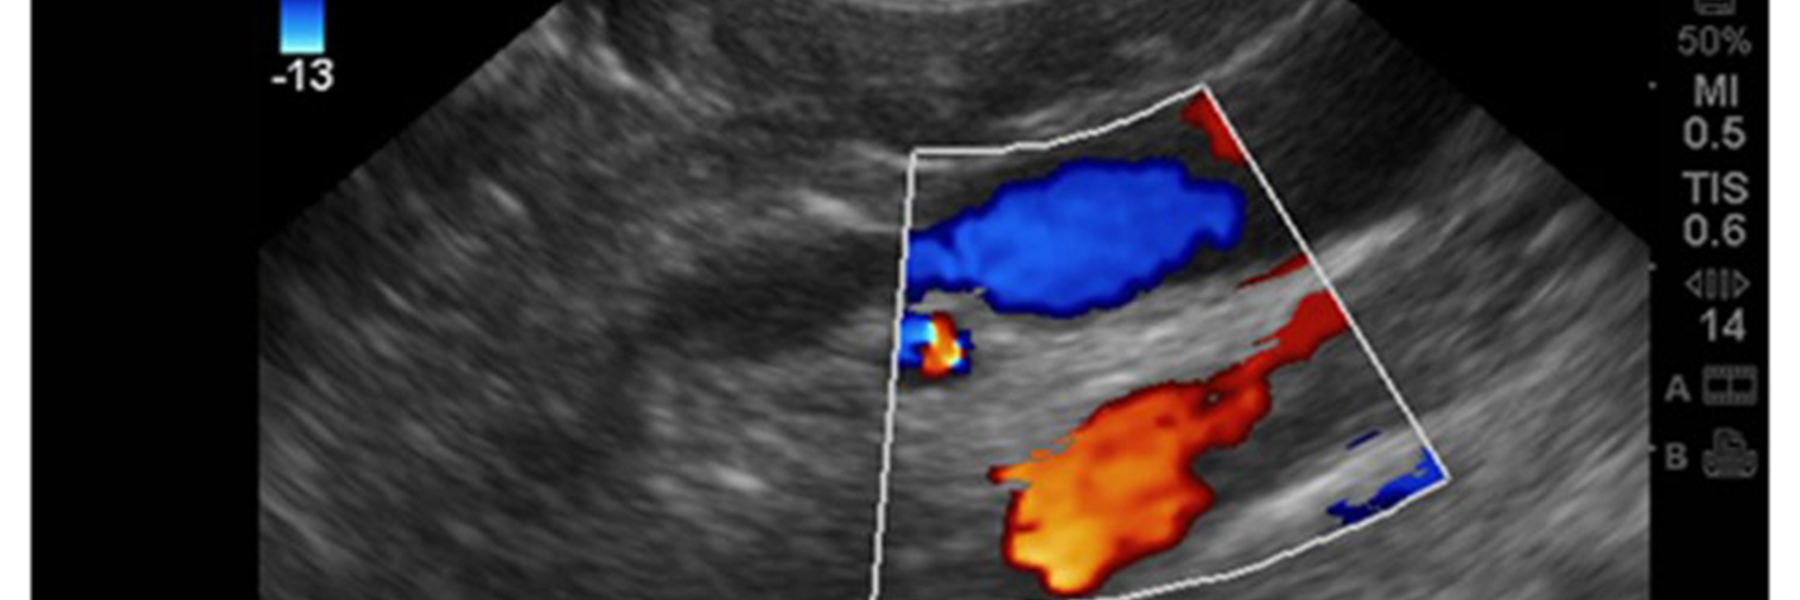

Colour Doppler Ultrasound

• Color Doppler. This type of Doppler uses a computer to change sound waves into different colors. These colors show the speed and direction of blood flow in real time.